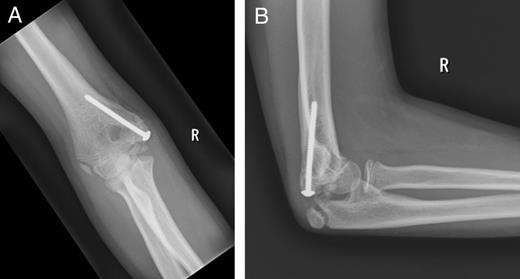

A 9-year-old girl presented to the emergency department with right elbow pain and swelling, after falling from a monkey bar onto her right elbow. She had no previous history of elbow or ulnar nerve problems. On examination, her right elbow was swollen, tender with limited movements. She had no history or clinical signs of an elbow dislocation, but she had a complete ulnar nerve palsy [with the absence of sensation and increased 2-point discrimination, Medical Research Council (MRC) sensation grading S0; MRC power grading 0/5 of intrinsic muscles of the hand, the little finger flexor digitorum profundus (FDP) and flexor carpi ulnaris (FCU); Froment's sign was positive), but there was no evidence of vascular compromise. A plain radiograph showed that the medial epicondylar apophysis had been avulsed into the ulna humeral joint space, but there was no other fracture or dislocation seen (Fig. 1A and B).

Plain radiographs of the injured right elbow: (A) anteroposterior view and (B) lateral view. Arrows highlight the avulsed medial epicondyle.